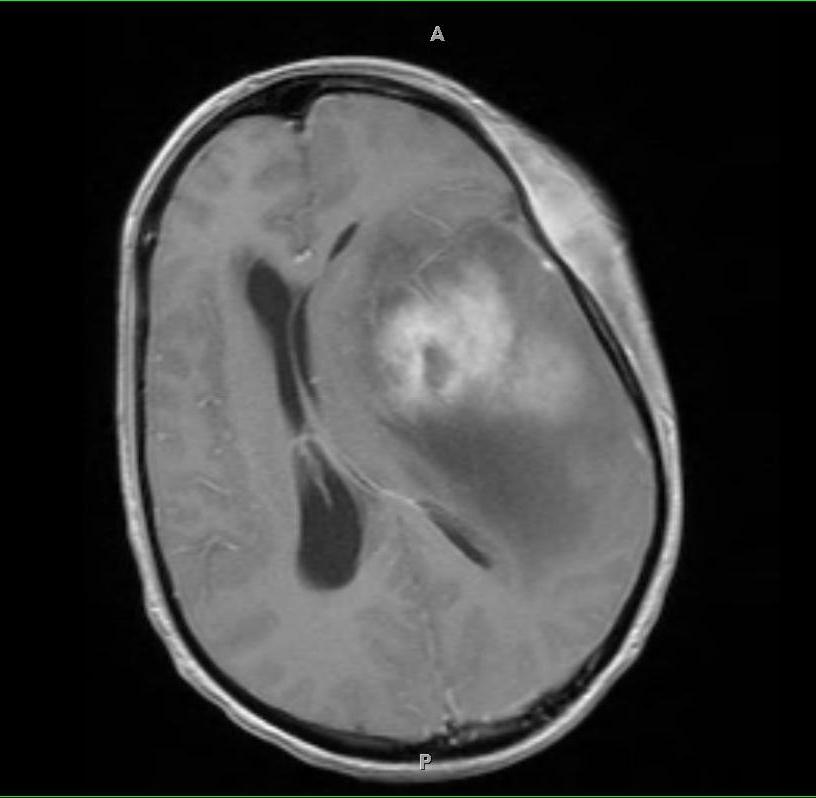

It was a Monday night. I was home having dinner with my family when I was paged by the resident covering our inpatient unit. My patient had just completed an MRI, ordered to help us determine why he had lapsed into a coma. The MRI had just been read, and the radiologist had called the resident with the result: not only had my patient’s tumor grown substantially, but it was causing an “uncal herniation” (this is when a part of the brain is compressed, often by blood or a tumor, cutting off the blood supply to vital structures and often rapidly leading to death). Since the family had already decided not to pursue further treatment of their child’s cancer, the progression was not a surprise, but I went back the hospital immediately to talk to them about the herniation, since that was a sign that their child could die as soon as that very night. The previous week, when asked how long they had left, I had estimated several weeks, so this change would come as quite a shock.